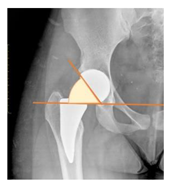

Plain radiographs were evaluated preoperatively and at the most recent follow-up, after appropriate calibration. Positional parameters were assessed according to values guidelines from published literature, as listed in Table 1 [23,24,25,26,27,28,29,30,31]. Femoral stem and acetabular cup osteointegration were quantified according to Engh [32] and Moore scale [33]. Heterotopic ossifications were graded according to the Brooker system [34].

3.4. Radiographic Evaluation

Preoperative and postoperative radiographic data are reported in Table 4. Preoperatively, 18 THR (24.3%) were implanted in skeletally immature children with closed triradiate cartilage (1 ≤ Risser ≤ 3). Radiographic acetabular insufficiency (LCEA < 25° and AI > 13°) was detected in 14 hips (18.9%), while protrusion was present in 3 hips (4.1%) An excessive valgus of the femoral neck was observed in 19 hips (25.7%), while an important varus deformity was present in 7 hips (9.5%).

Postoperative radiographs showed a significant vertical malposition of the cup in 1 case (1.4%), a significant varus stem in 8 cases (10.8%) and a significant valgus stem in 1 case (1.4%). Two patients (2.7%) showed moderate heterotopic bone formation (Brooker ≥ 2), that did not significantly affect the hip motion and symptoms. All those THR that did not undergo revision showed good radiographic osteointegration, with no evidence of implant breakage, radiographic lucencies, bone defects, cup migration, or stem subsidence at the most recent radiographs.

In our experience, implant malposition was the only reason for implant revision. In one case, progressive subsidence was observed in a varus undersized stem, implanted in a boy with Albers–Schömberg disease; in another case, an excessively vertical cup with a 28 mm femoral head caused hip instability and required cup revision.

THR can be a challenging procedure in very young people. The combination of distorted anatomy, small physique, and poor bone stock can impede proper implant placement. Implant sizing may be an issue in these patients. The combination of young age and peculiar conditions such as skeletal dysplasia may require particular attention in preoperative planning and implant selection. Noticeably, we used the smallest size of the cup in 11 hips (15%) and the smallest size of the stem in 14 hips (19%). A meticulous preoperative planning, even using simulation software, [40,41,42] and careful implant selection, sometimes requiring even customized implants [37], is crucial in such conditions, to prevent unpleasant pitfalls during the operation.